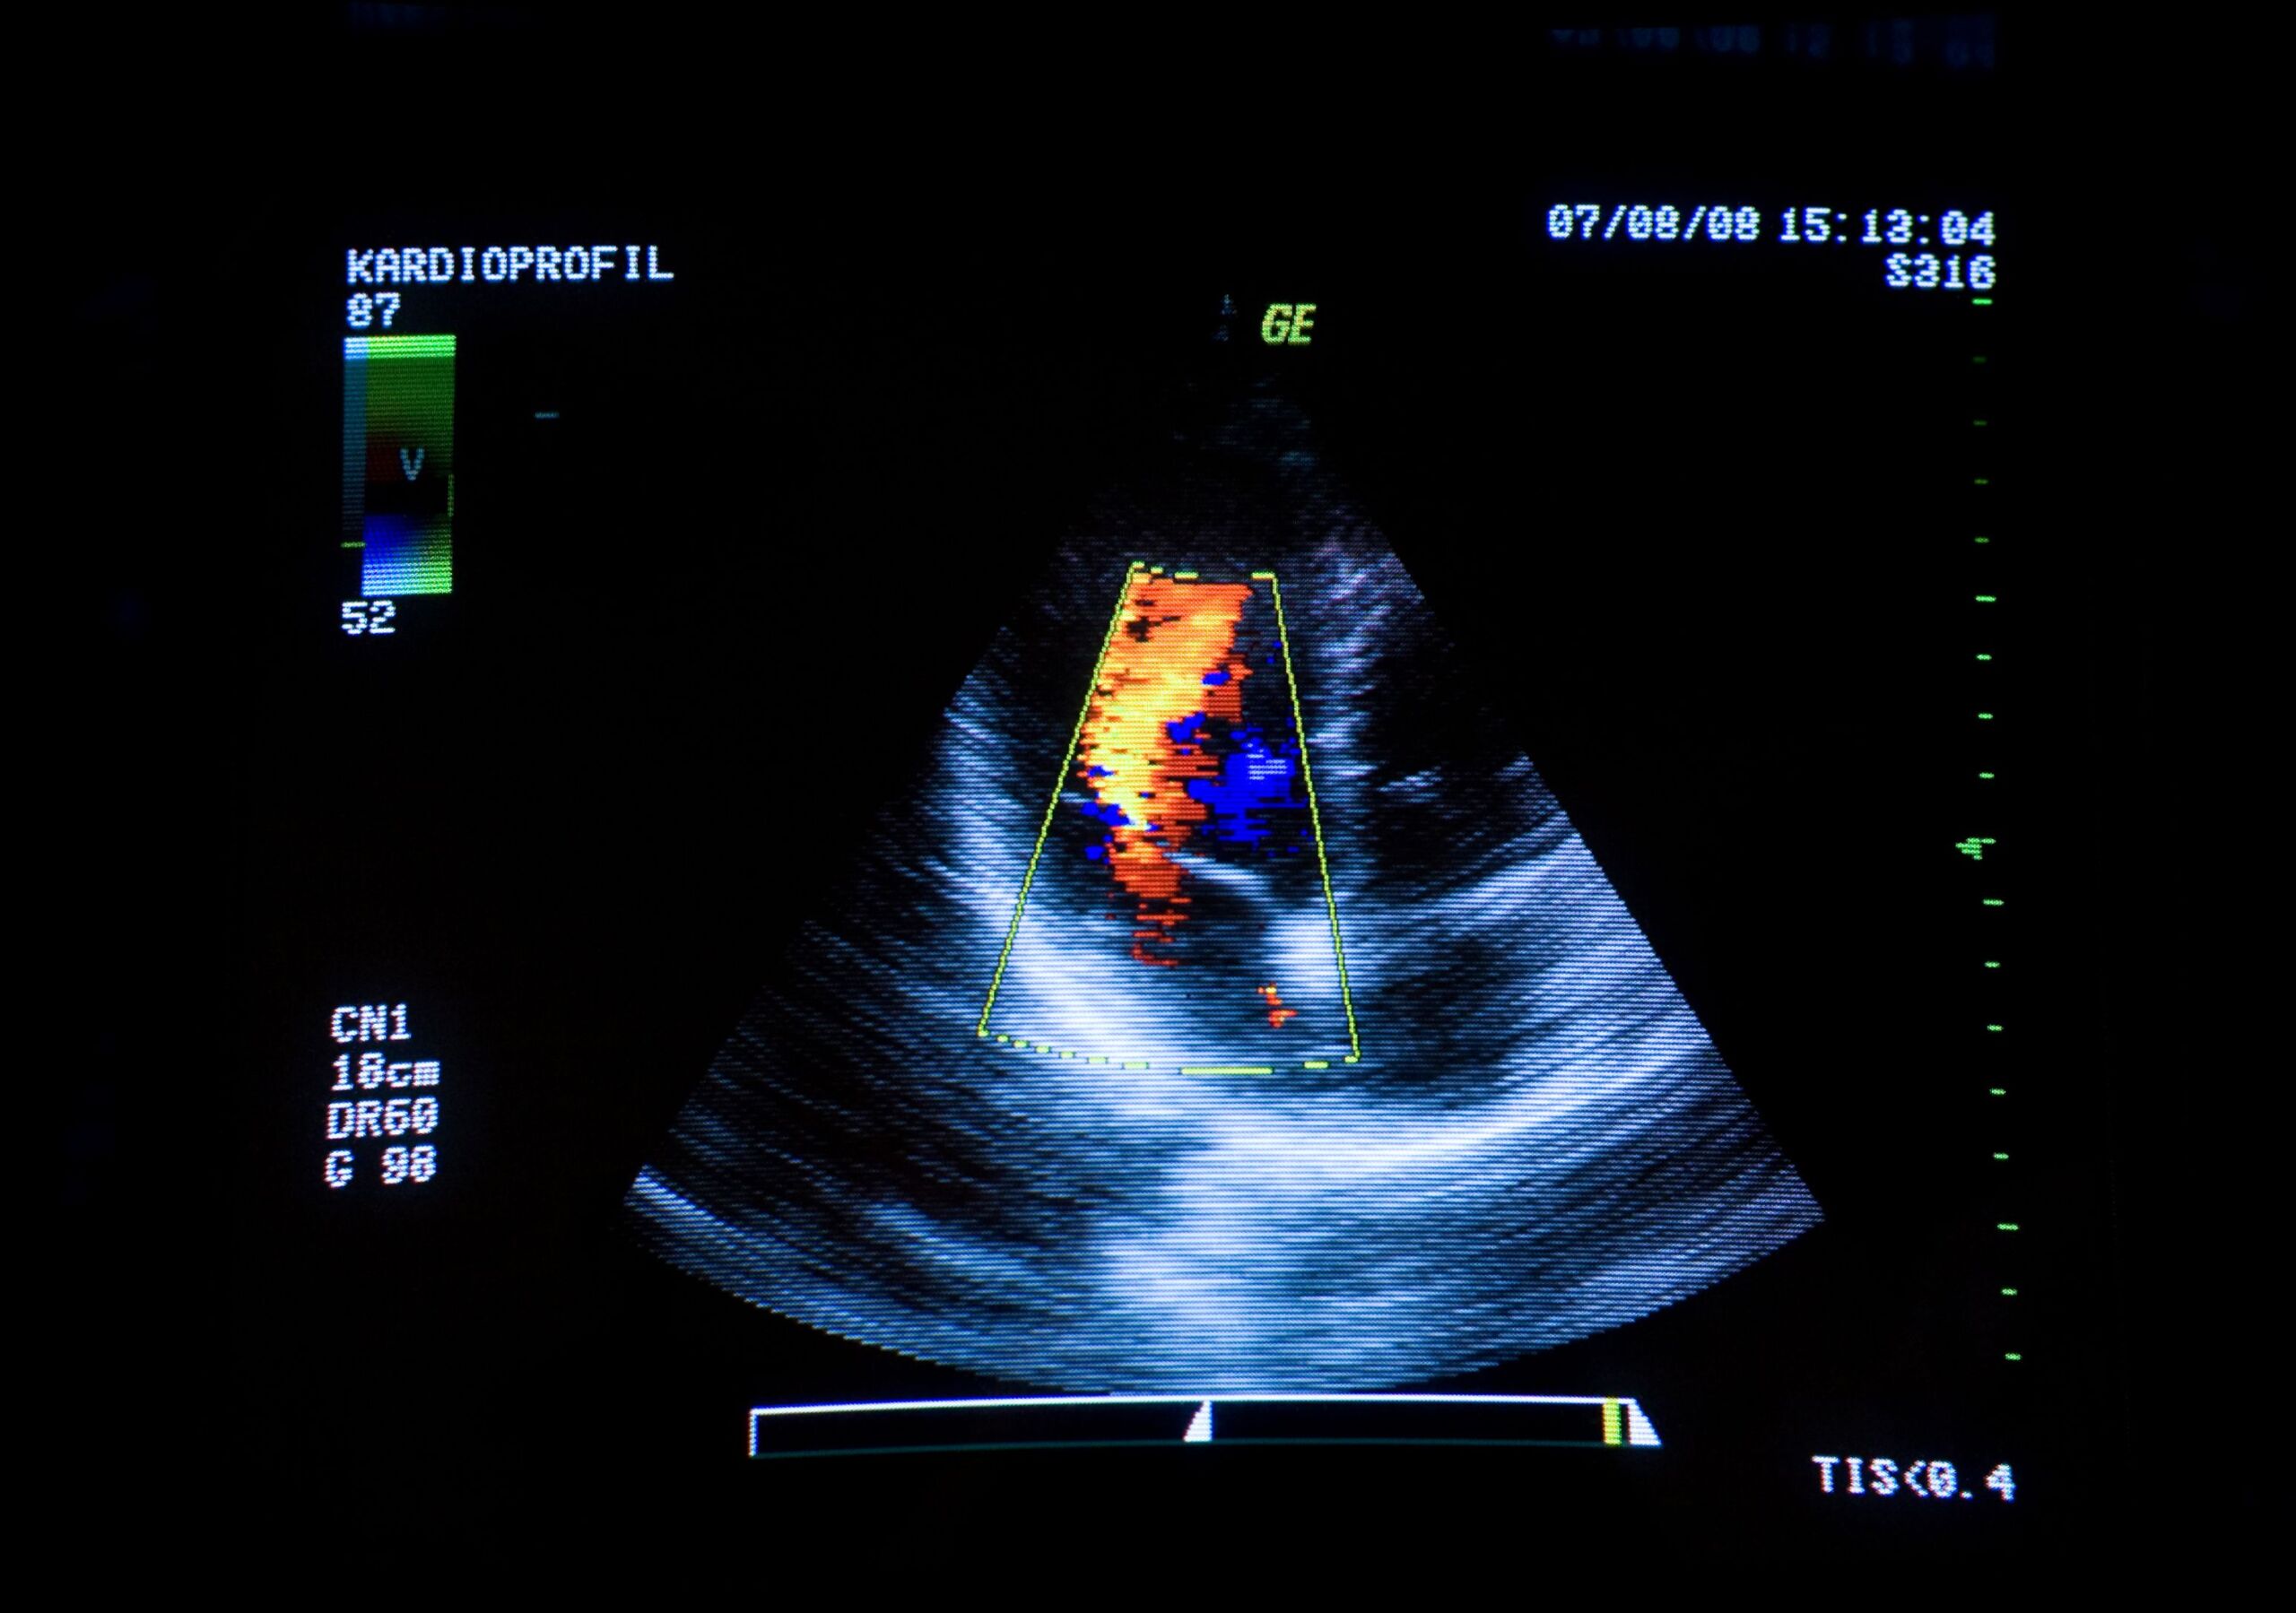

Heart Disease Detection

Grow your cardiovascular program and automatically identify your patients at risk of structural heart disease with unparalleled speed and accuracy with Echo IQ.

Detect Aortic Stenosis with Unparalleled Efficiency and Accuracy

Cassling has partnered with Echo IQ to bring you EchoSolvTM, an AI platform used to aid in the accurate detection of aortic stenosis.

Through an automated assessment, EchoSolv leverages the largest global database of echocardiograms linked to mortality to identify patients at risk for aortic stenosis in less than three seconds. EchoSolvTM uses a multi-dimensional heart profile and clinical guidelines to identify 100% of patients at high risk of having in-guideline aortic stenosis .

The Power of Deep Learning on the Entire Heart

The only AI platform built on the largest database of echos linked to mortality in the world, Echo IQ’s technology has the potential to improve patient quality of care, assist interventional cardiologists in more accurately and easily detecting Aortic Stenosis, reduce costs for healthcare facilities, and reduce unconscious bias, helping to standardize and improve care across facilities and regions.